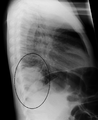

| A chest X-ray showing a very prominent wedge-shape bacterial pneumonia in the right lung. | |

Right upper lobe pneumonia as marked by the circle.- Left upper lobe pneumonia with a small pleural effusion.